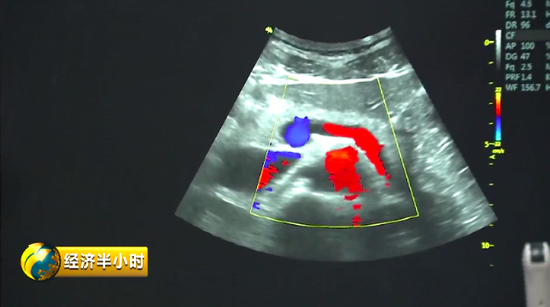

彩色B超 有一个特殊的彩色B超设备,不仅能够精确诊断,还能帮助大夫有效地给予患者治疗。也就是说,在治疗疾病时,在超声波的介入下,药物被精准送达病变位置,释放药物,从而实现靶向治疗。而且这个彩色B超设备副作用很少,安全性特别好。《经济半小时》记者在苏州工业园区了解到,目前这种彩色B超设备在国际上已经达到一流水平。